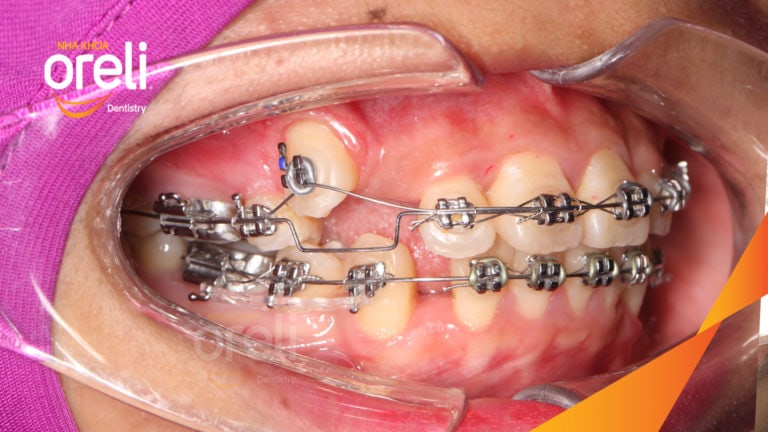

Ca niềng răng sai khớp cắn hạng 3 móm nặng có nhổ răng số 7 – Kết quả thực tế Niềng răngChỉnh lệch cằmMóm Xem thêm